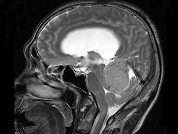

- 单项选择题男,61岁, 头晕头痛伴行走不稳1月余,请根据所提供图像, 诊断最有可能是 ( )

A、转移瘤

B、胶质瘤

C、淋巴瘤

D、髓母细胞瘤

E、(天幕切迹缘)脑膜瘤